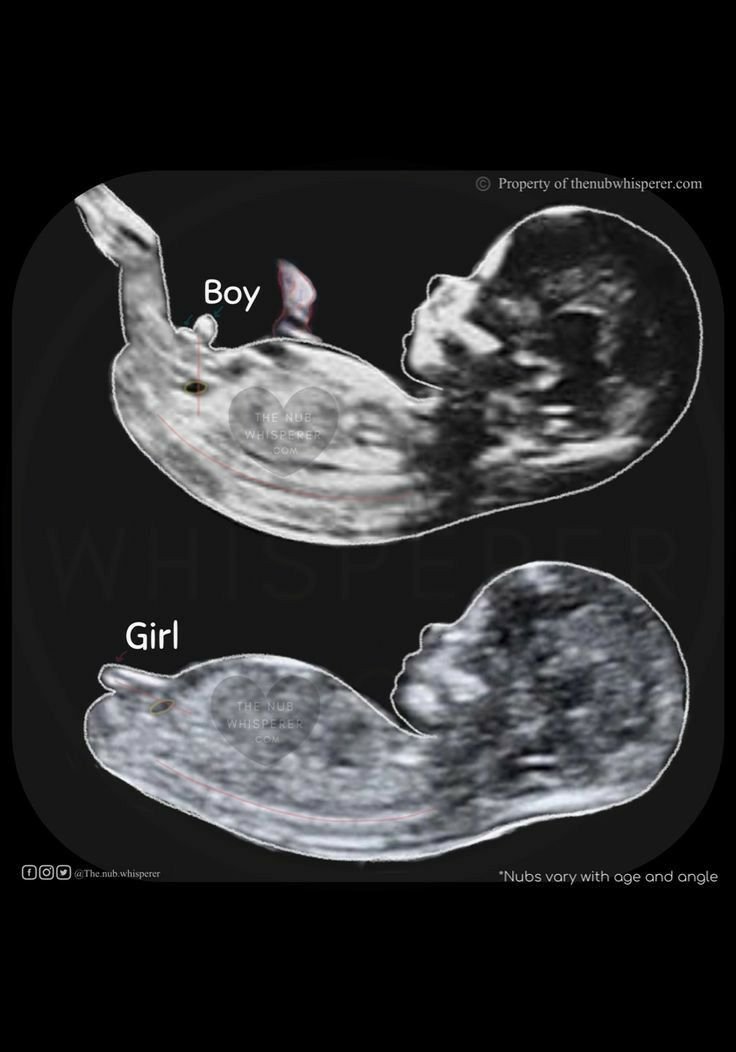

В 12г.с. всъщност изглежда по много сходен начин между крачетата при двата пола. В скрит текст допълвам, за който иска да се ориентира на ехографа.

Различават се единствено по посоката, която сочи спрямо гръбначния стълб. При момичетата е успоредно на гръбначния стълб или с ъгъл под 30 градуса, а при момчетата е перпендикулярно на гръбначния стълб или с ъгъл над 30 градуса. Вижда се точно само при изглед в профил. С напредване на бременността вече от това "образувание" се формират мъжки или женски полови органи.